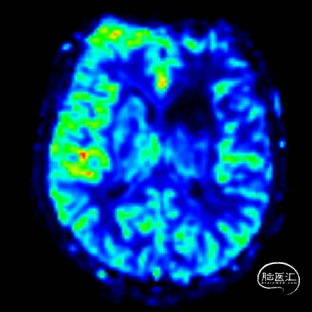

术后即刻影像。

支架植入后造影提示残余狭窄约10%。术中患者生命体征稳定,术后患者恢复良好出院,继续抗血小板聚集及他汀类药物治疗。